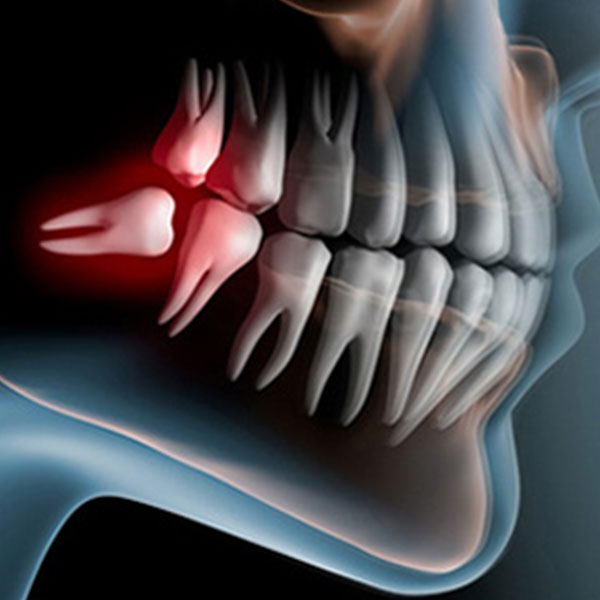

Vađenje impaktiranih zuba, Resekcija korena zuba, Operacije viličnih cista, Hirurgija maksilarnog sinusa, Recesija gingive, Oslobađanje zuba u ortodontskoj terapiji.